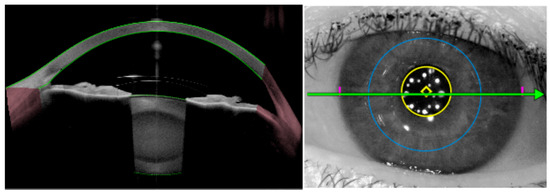

Background and Objectives: Optic disc drusen (ODD) can mimic papilledema and are linked to structural crowding, microvascular change, and visual-field loss. We synthesized structural/microvascular differences, functional status and change, diagnostic...